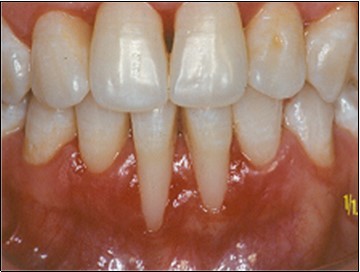

Figure 2.After initial therapy

After initial therapy

Recipient Site

A partial thickness flap is created with two vertical incisions placed at least one-half to one tooth wider mesiodistally than the area of gingival recession. The coronal margin of the flap is started with a horizontal sulcular incision to preserve all existing radicular gingiva. The interproximal papillae are left intact. The flap dissection is partial thickness leaving connective tissue over the existing bone and / or root surfaces. The root of the involved tooth is carefully scaled and planed until its surface is smooth and hard. Er-YAG laser is then applied to its surface to promote root biomodification, at powers ranging from 25 to 50 mJ/pulse/sec. (Figure 3, Figure 3A).